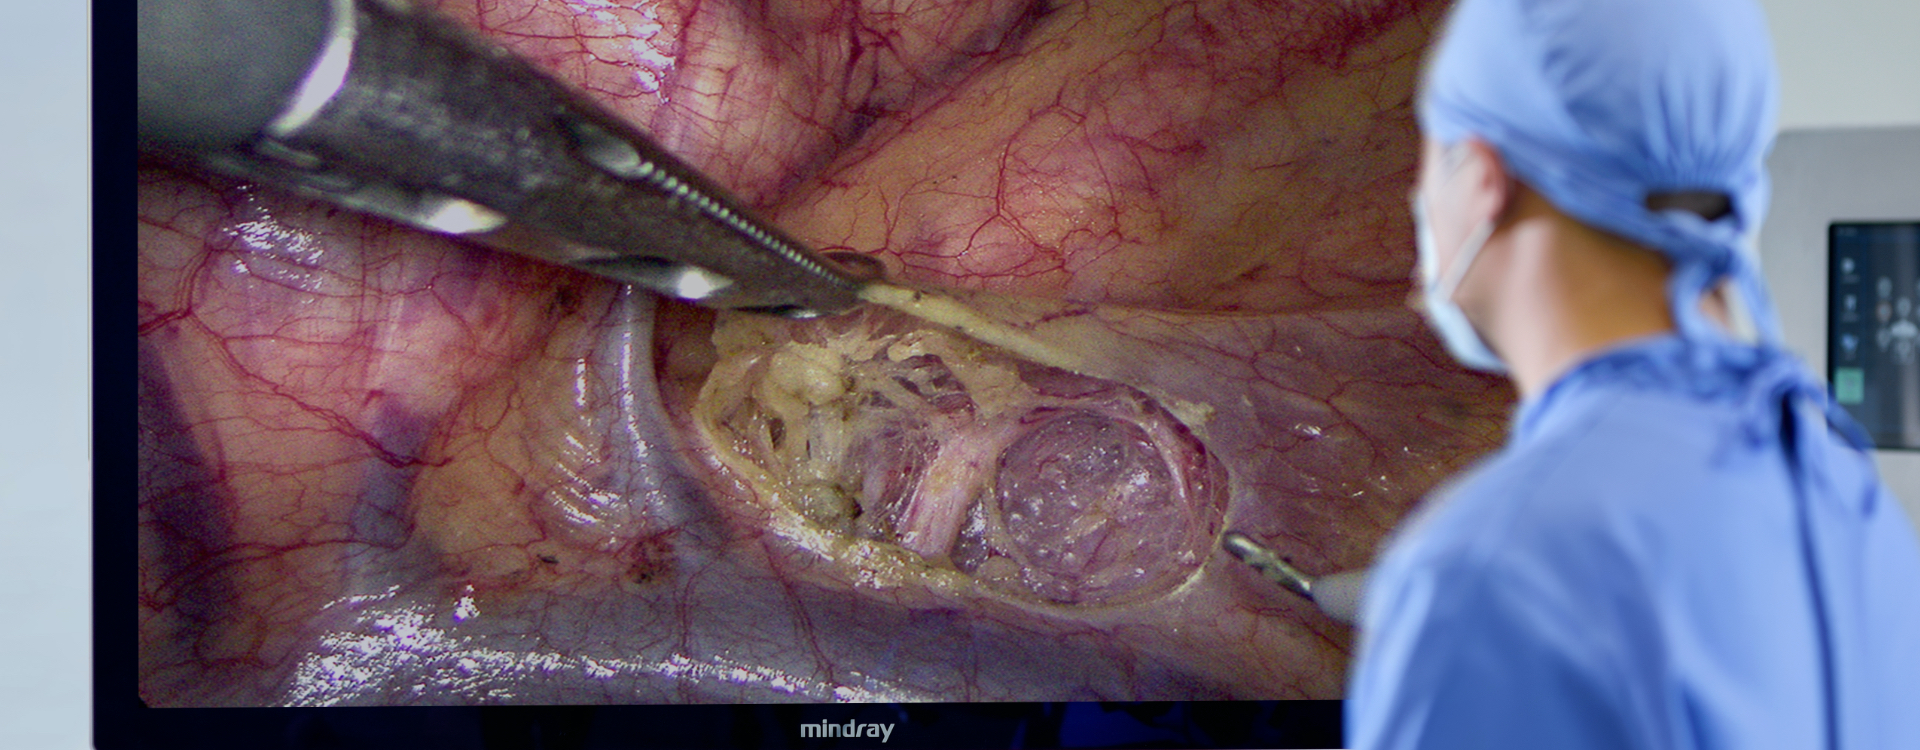

RĂŠsolution 4K

Offre une image ultra-haute dĂŠfinition avec une rĂŠsolution de 3840Ă2160.

Large gamme de couleurs

Restitue les organes et les tissus avec des couleurs authentiques ; identification parfaite des vaisseaux sanguins, des ganglions lymphatiques et des nerfs.

3 Ă 200 mm de profondeur de champ

La mise au point reste nette lors du passage d'une scène de fonctionnement à une autre.

Une expĂŠrience immersive de 55 pouces

L'image chirurgicale est agrandie sans rĂŠduire la rĂŠsolution, de sorte que les dĂŠtails ne sont plus petits et que la fatigue visuelle du mĂŠdecin est rĂŠduite.